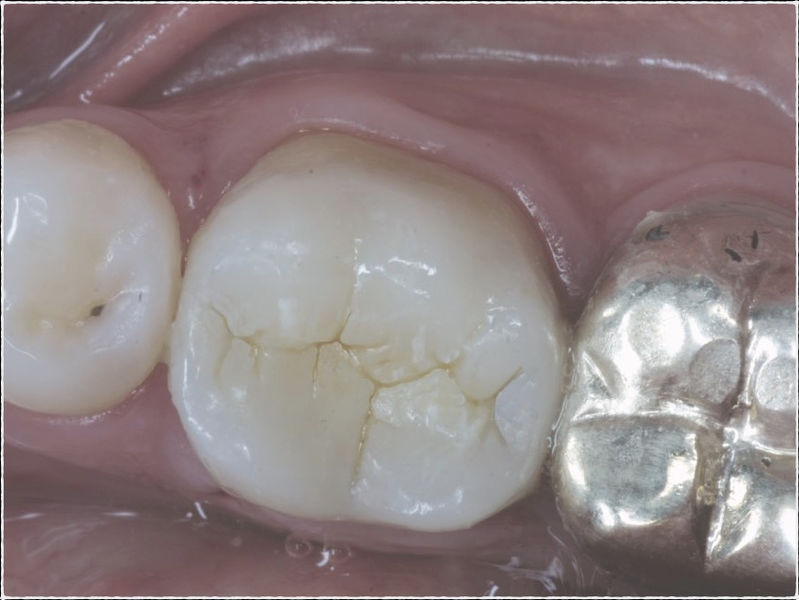

Restauraciones fabricadas en el laboratorio con materiales estéticos, los cuales cubren de manera total dientes anteriores y posteriores. Se utilizan primariamente para restaurar dientes con caries, fracturas y/o defectos amplios, así como soportes de puentes. Para poder enviar el caso al laboratorio se toman impresiones utilizando materiales de impresión o técnicas modernas digitales.